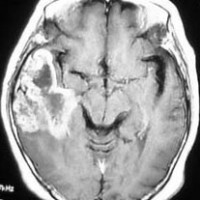

典型的な膠芽腫のガドリニウム増強画像です。右の側頭葉から発生したために目立った症状が無く,この大きさで発症しました。何となくボッとしていると言うのが訴えでした。腫瘍の周囲がガドリニウムで白く増強されて,内部は壊死で低信号(黒っぽい)になっています。